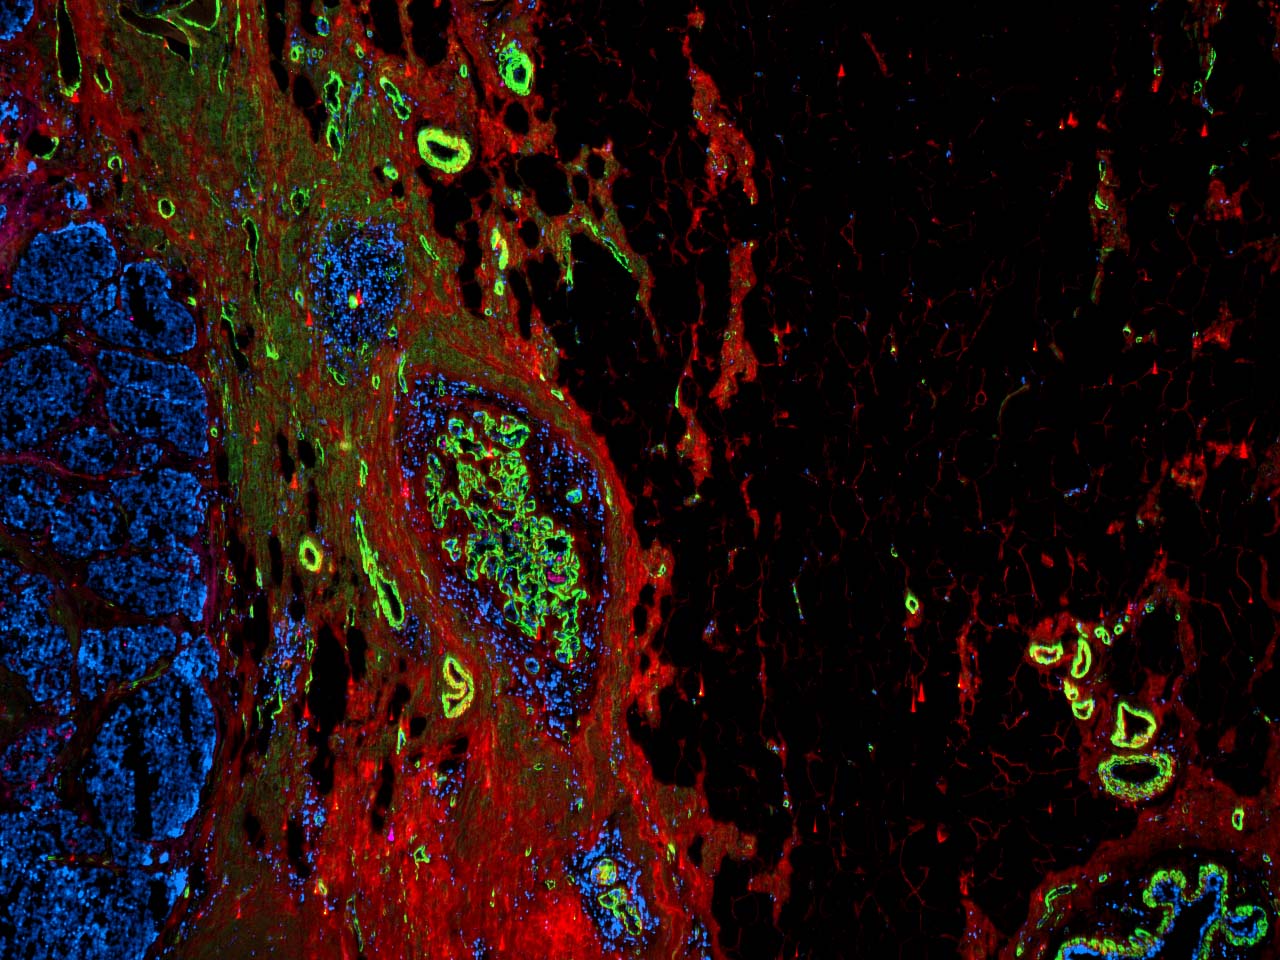

Munson Lab Vt . The munson lab studies the tumor microenvironment in cancers, including glioblastoma, the deadliest form of brain cancer. Our research program aims to understand and harness the tumor microenvironment to study and treat triple negative breast cancer and. Jenny munson is a principal investigator at the fralin biomedical research institute who studies the tumor. Our research focuses on the. Led by principal investigator jenny munson, ph.d., director of the fralin biomedical research institute cancer reearch group, the munson. Jennifer munson, associate professor at the fralin biomedical research institute at vtc, shared her data on fluid flow in brain tumors with virginia. In 2019, he started his postdoctoral research at ucsf in dr. Engineering cancer to cure it. Jennifer munson, associate professor at the fralin biomedical research institute at vtc, shared her data on fluid flow in. Our mission is to investigate and evaluate the tumor microenvironment, the tissue around a tumor that is involved in invasion and metastasis.